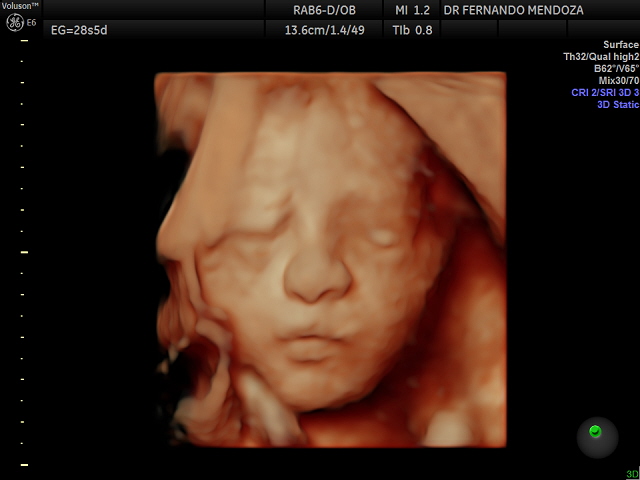

Dr. Fernando Mendoza Calderón

¡Bienvenidos al perfil del Dr. Fernando Mendoza, un distinguido profesional de la salud dedicado a la ginecología y obstetricia, con una especialización en enfermedades de mama! Con una amplia experiencia y profundo compromiso con la salud femenina, el Dr. Mendoza se destaca como un referente en su campo.

Con una trayectoria impecable, el Dr. Mendoza ha atendido a numerosas pacientes con una atención personalizada y compasiva. Su enfoque integral en la prevención, diagnóstico y tratamiento de enfermedades de mama, lo convierte en un aliado valioso para la salud mamaria de sus pacientes.